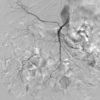

4

Q

A

superior mesenteric artery